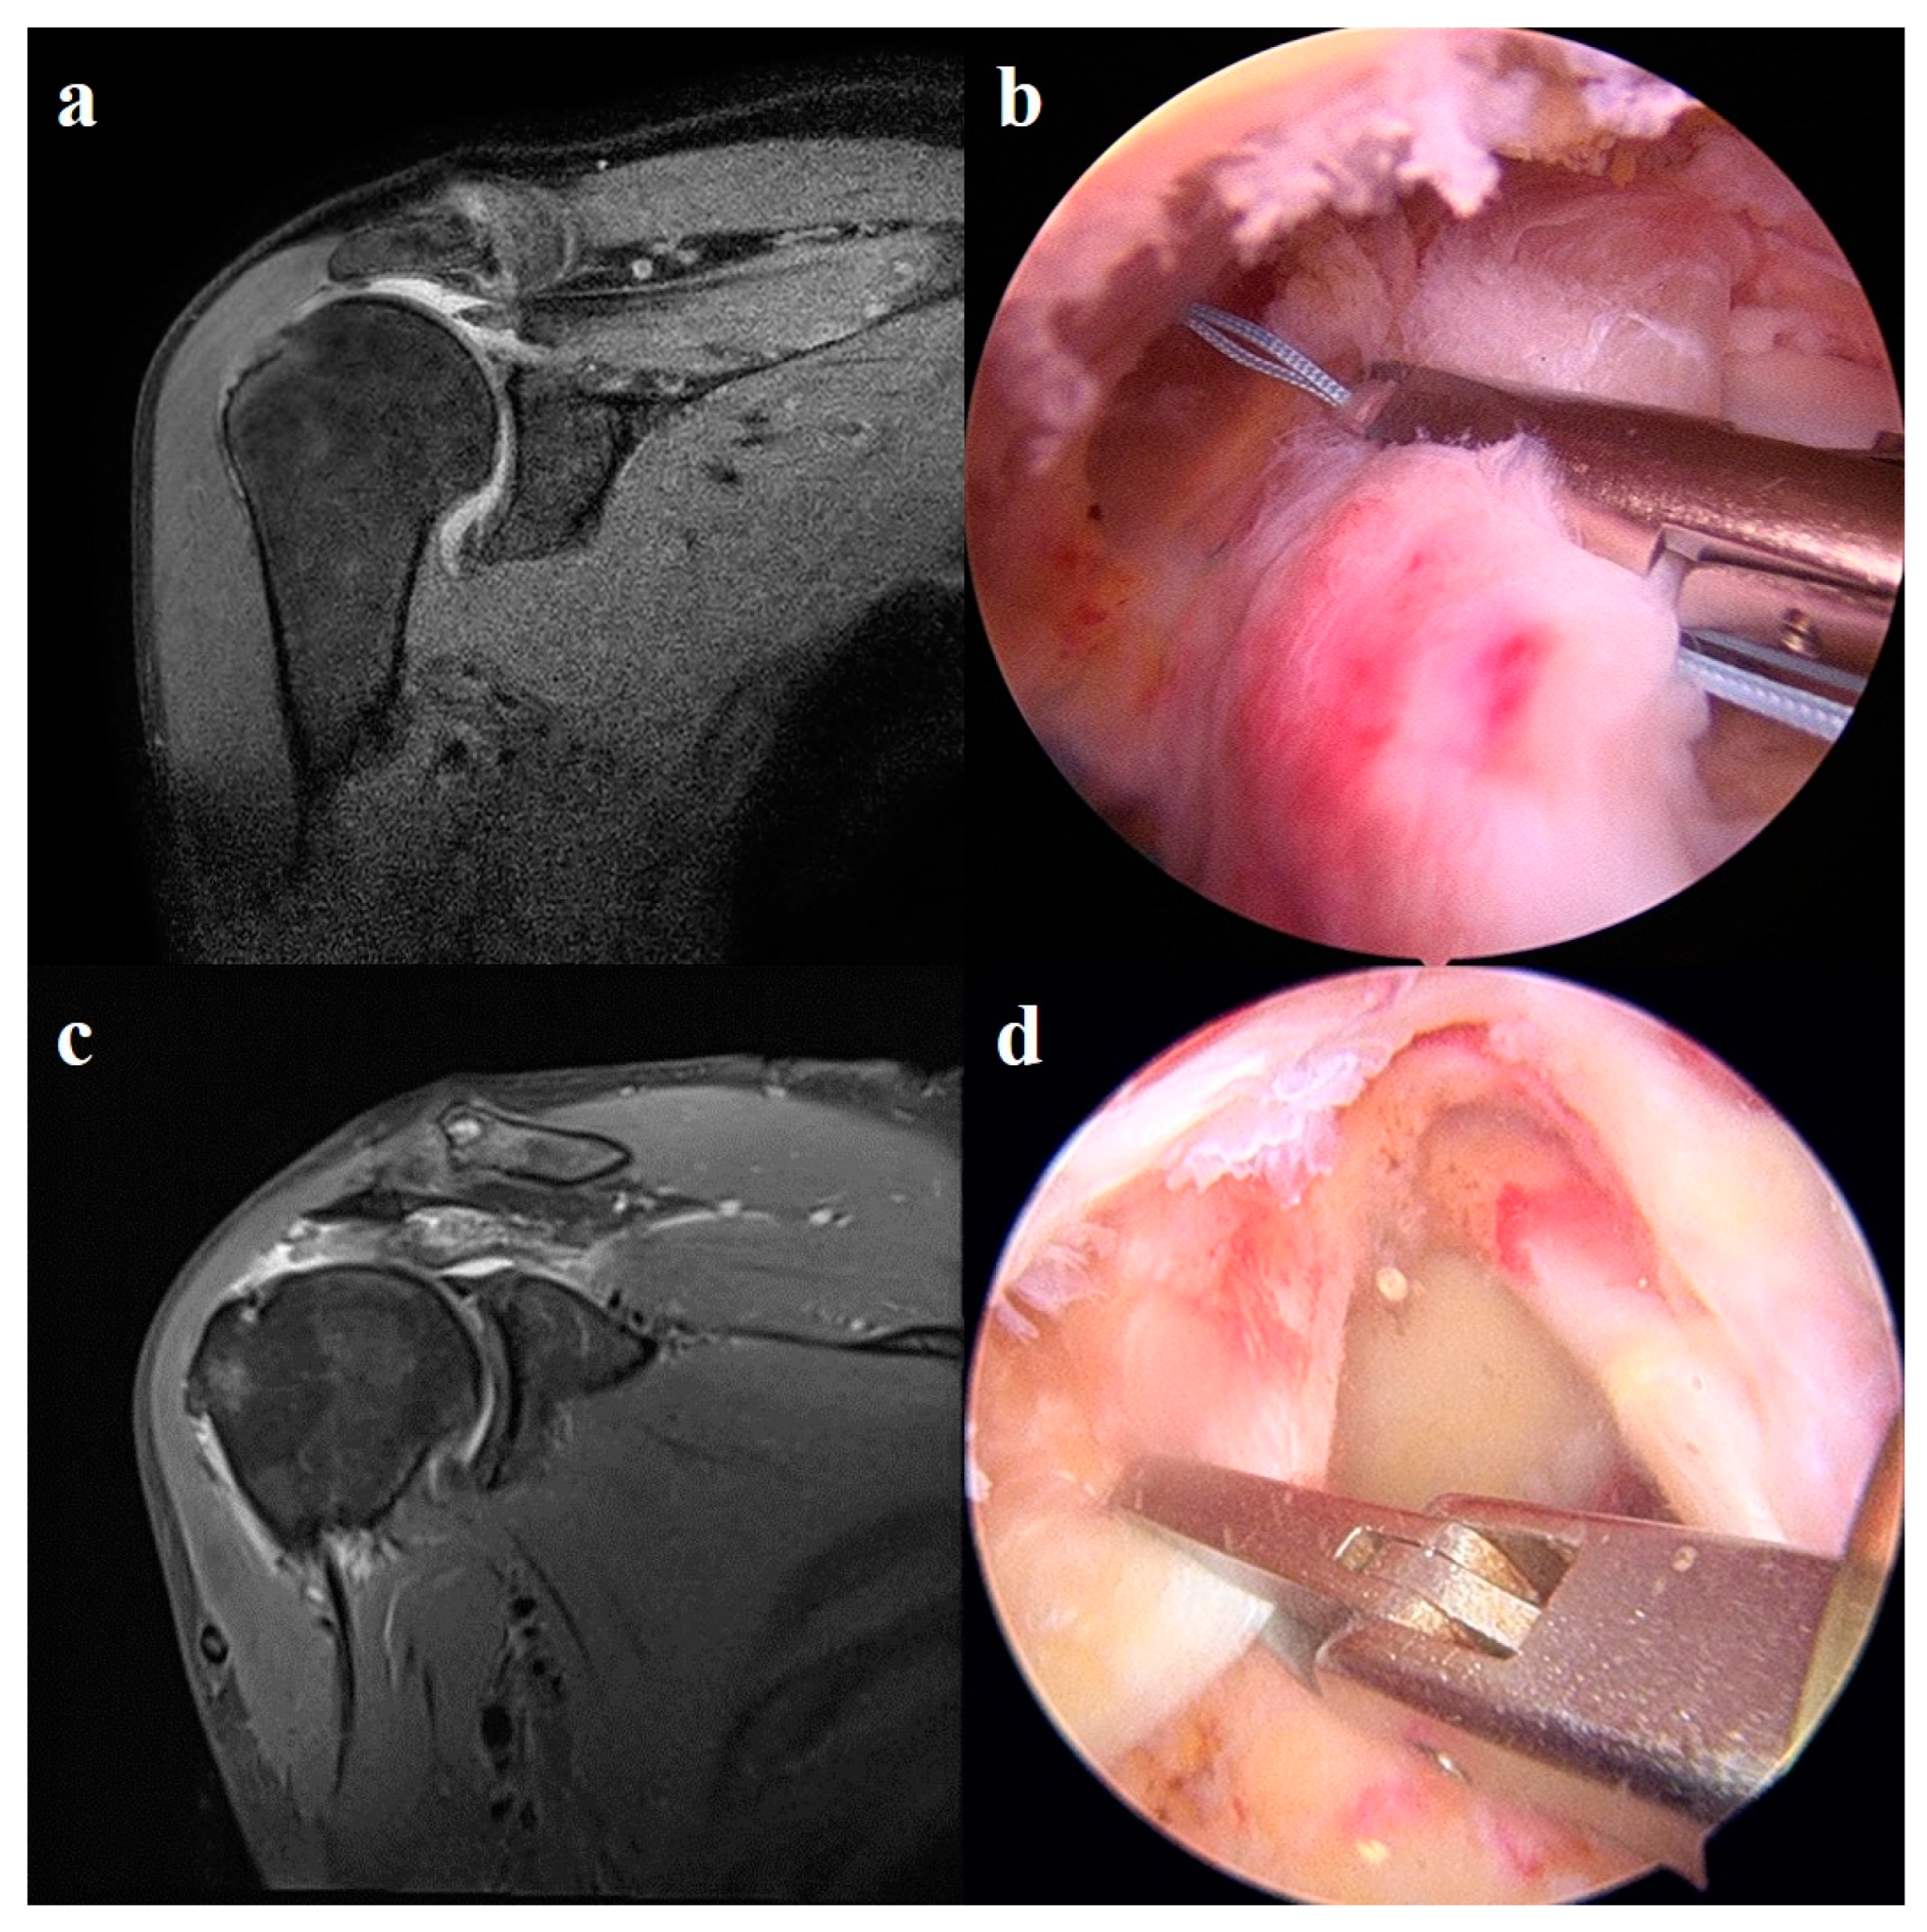

2.5. Surgical Technique

2.5.3. Patch Graft Augmentation